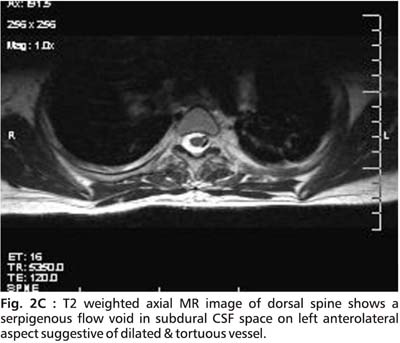

An initial MRI cervical spine revealed cervical cord edema at C5 to C7 ( Fig.1). A repeat MRI done after 15 days showed striking changes in the same area (Fig. 2A, 2B, 2C and 2D).

The cervical MR findings are suggestive of subacute spinal subdural hemorrhage appearing hyperintense on both T1 and T2 images. Serpigenous flow voids were seen on axial sections suggestive of Arterio-Venous malformation (AVM). Unfortunately, a subsequent angiographic study could not be done.